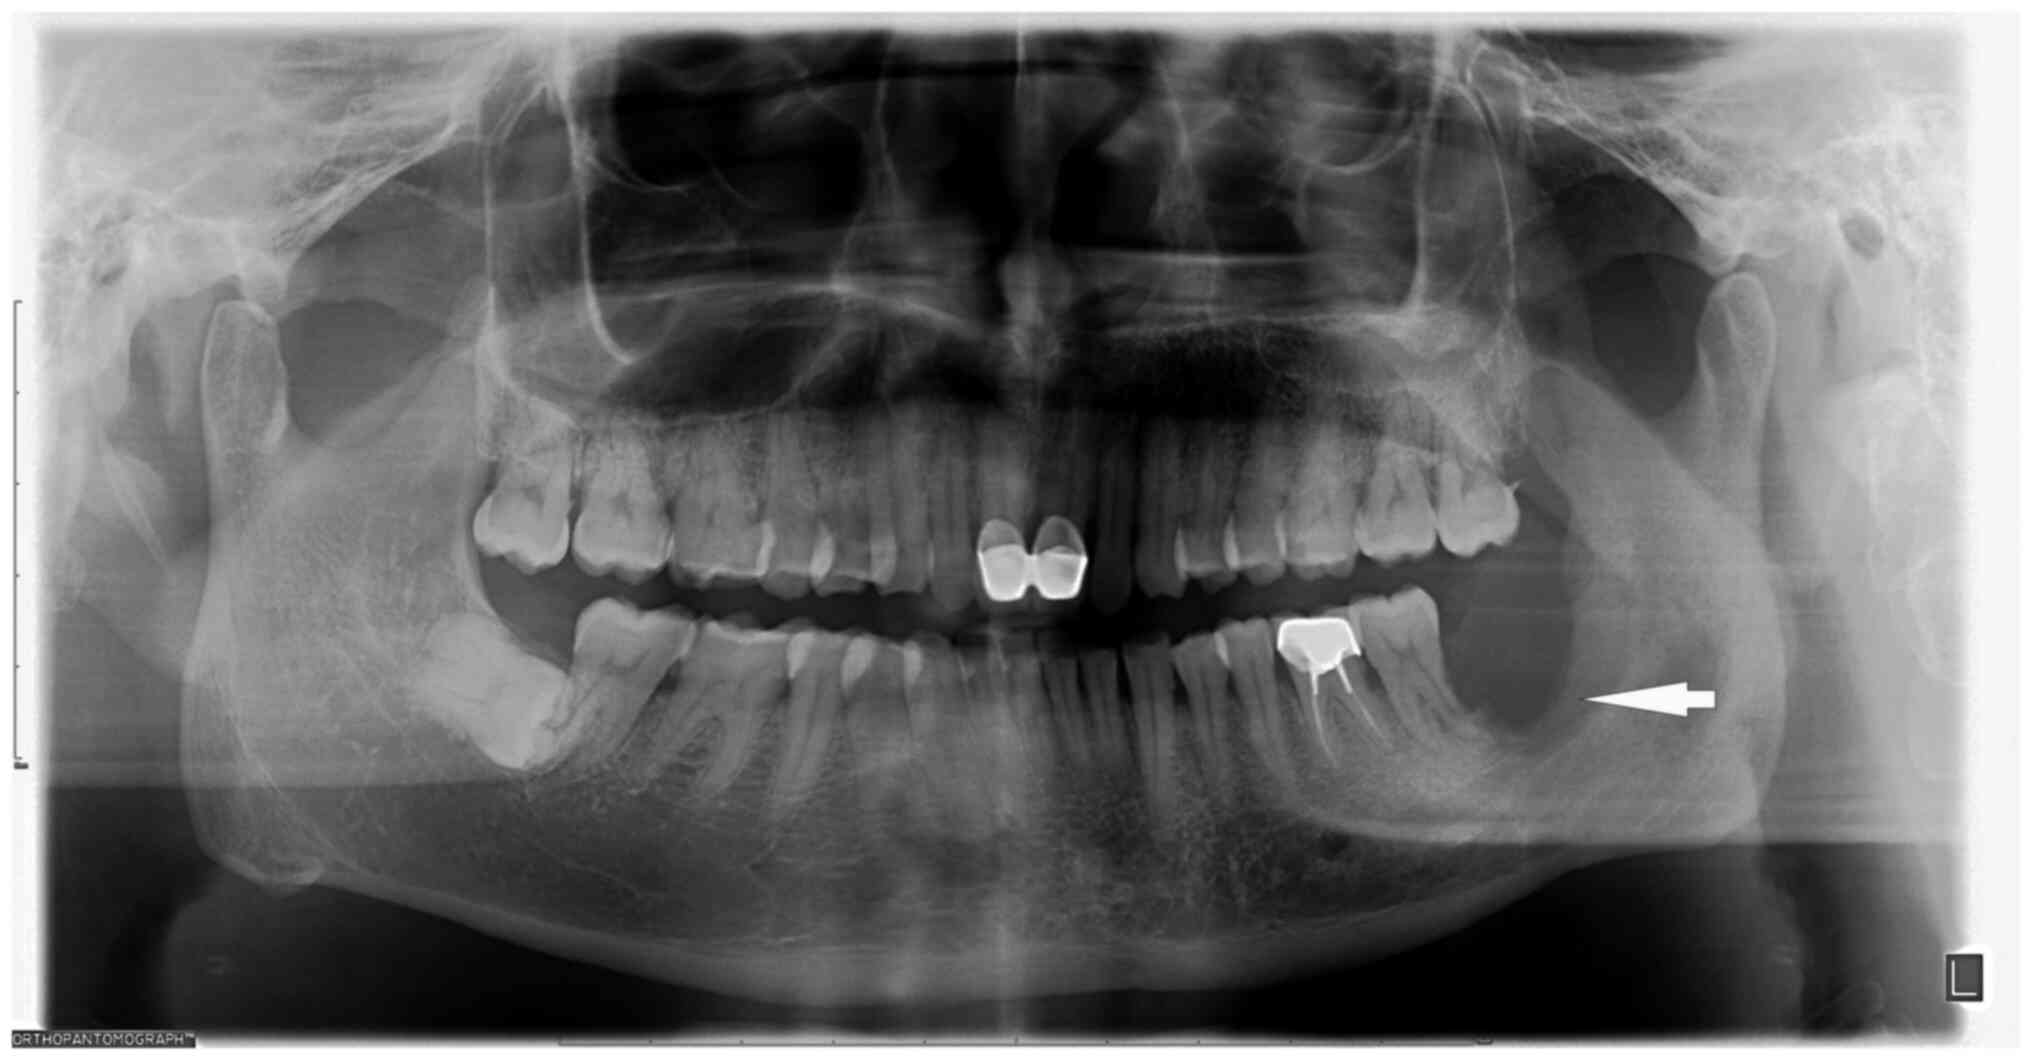

Figure 1

Panoramic radiograph prior to admission. The lower left third molar was missing, with resorption of the alveolar socket extending to the root apex area of the lower left second molar. In addition, a 0.5x1 cm low-density shadow with an indistinct boundary was discernible in the middle and lower portion of the left mandibular ascending branch (arrow).

Radiographic assessments were based on reports from two or three independent radiologists. Panoramic radiographs revealed that the lower left third molar was missing, with resorption of the alveolar socket extending to the root apex area of the lower left second molar. In addition, a 0.5x1-cm low-density shadow with an indistinct boundary was discernible in the middle and lower portion of the left mandibular ascending branch (Fig. 1). At the sagittal plane (Fig. 2A), mandibular CT scan showed involvement of the left mandibular coronal process and ascending mandibular rami. Cross-sectional perimetry (Fig. 2B) revealed a local lamellar periosteal reaction with an increase in bone mineral density in unaffected areas. The coronal visual field (Fig. 2C) showed significant destruction of the left ascending branch of the jaw with a soft tissue mass. A 3D surface reconstruction (left maxillary surface, Fig. 2D) highlights the deformation of the left mandibular coronal process, rami, and body. Given these findings, concerns were raised regarding the possibility of an invasive or malignant bone tumor. After admission, a preoperative tissue biopsy was performed on the left mandibular lesion. The collected tissue, obtained from the affected site, underwent histopathological examination with Hematoxylin and Eosin (HE) staining. The diagnosis of squamous cell papilloma was conclusively confirmed based on the distinctive features observed in the stained biopsy specimens. Consequently, it was determined that complete resection represented the optimal course of action for the patient. The surgical procedure was performed by an oral and maxillofacial surgeon. A grayish-yellow mass measuring 3.0x2.0x1.5 cm was identified in the left masseter attachment area during the operation, which exhibited a texture akin to the tip of the nose, tough with medium consistency, and had unclear boundaries. In total, ~0.5 cm of the tissue surrounding the tumor was excised. No destruction was observed on the buccal side of the left mandible. The bone surface appeared waxy and rough, involving blurred boundaries. Numerous grayish-white papillary growths (white arrow) were visible along the left ascending mandibular branch (Fig. 3A). A resection involving the left mandibular body, the left ascending branch of the mandible and the coronal process was performed to address this diseased bone. Finally, a bone plate harvested from the medial iliac ridge of the left side was utilized to fill the bone defect within the left mandible. To ensure adequate fixation, the defect was secured using titanium plates and titanium nails. In the assessment of this mass, the primary goal was to differentiate between benign papilloma and squamous cell carcinoma, necessitating a meticulous analysis of cellular characteristics. The focus was in identifying any indicators of cell atypia, heightened mitotic activity and aggressive traits suggestive of malignancy. Furthermore, the presence of a distinct papillary structure supports the exclusion of squamous cell carcinoma. Clinical relevance, imaging studies and the expertise of two independent pathologists further bolster our ability to rule out malignancies from the list of potential diagnoses.